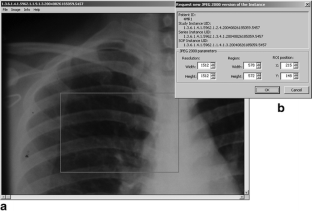

The idea for softcopy viewing of medical image outside the radiology reading room spread among the scientists in various fields for several years. An image could be read on workstation of all types, from desktop across movable to handheld. Benefits are numerous and continue to grow as physicians use them discovering new usage cases. Proposed solutions vary with PACS architecture invasion level, communication and storage image formats, and utilization. We employ JPEG2000 standard because of its high (lossy/lossless) compression ratio with minimal spatial distortion, retrieval-oriented storage, and streaming. It is embedded in PACS as the DICOM Private Data Element containing JPIP parameter string, so-called DICOM2000. The DICOM2000 message is transparent for standard DICOM devices at the slightest level of invasion. Thanks to sophisticated JPEG2000 streaming, medical image becomes suitable for any resolution and quality display and (wireless) networks. The solution is validated on the ACR/NEMA standard test set of PACS images.